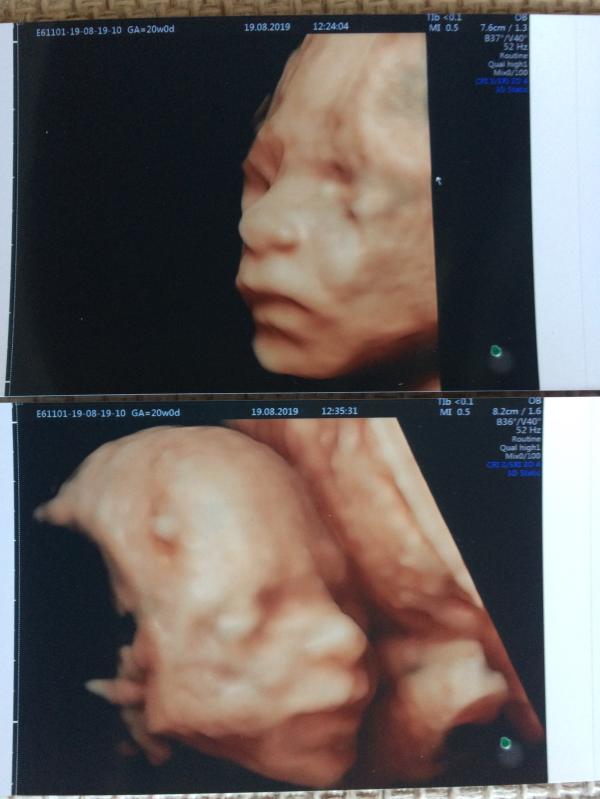

Вчера был второй скрининг, все хорошо, котёнок растёт 😊 400 грамм 😊 по узи 21 неделя)